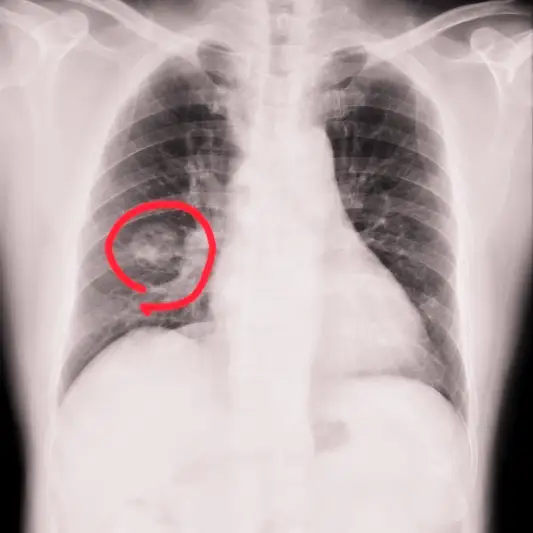

폐암 1기 진단을 위해서는 정기적인 검진이 중요합니다. 폐암 검진에는 흉부 X-선, CT 스캔, PET 스캔 등이 사용될 수 있습니다. 이러한 검사를 통해 의사는 폐암의 존재 여부와 정확한 위치를 확인할 수 있습니다. 또한 폐암의 크기, 종류, 세포의 특성 등을 파악하여 적절한 치료 방법을 결정할 수 있습니다.

폐암 1기는 폐조직 내에서 악성 종양이 형성되었음을 의미합니다. 이 단계에서는 종양이 아직 주변 조직으로 번지지 않고 지역적으로 제한되어 있습니다. 따라서 초기 폐암 치료는 주로 수술로 이루어집니다.

폐암 1기 치료의 주요 방법은 수술입니다. 수술은 종양이 있는 부분을 완전히 제거하는 것을 목표로 합니다. 이를 위해 일반적으로 경피적폐생검(CT가이드하에 종양을 수집하여) 후 확진된 환자에게는 말초폐부분절제술(혹은 폐절제술)이 시행됩니다.